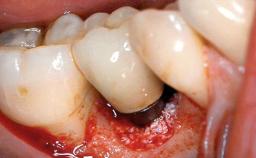

A male patient had lost teeth 11 and 22 as a result of a bicycle accident at age 14. In his adolescent years, a removable prosthesis had replaced the missing teeth. At age 21, the patient was referred by his dentist to the university clinic for treatment of the missing teeth 11 and 22 with implants. He was in good health and a nonsmoker. The absence of teeth 11 and 22 over many years had led to significant atrophy of the alveolar ridge, particularly at site 11. As a first step, the alveolar ridge was augmented using a block graft to replace the lost bone. A Straumann SP implant (diameter 4.1 mm, length 12 mm; Institut Straumann AG, Basel, Switzerland) and a Straumann Narrow Neck implant (length 10 mm) were inserted in the correct location and axial position at sites 11 and 22, respectively, six months later. After three months of healing and subsequent reentry, the patient returned to the referring dentist to receive the prosthetic restoration. The patient was seen again six months after the restoration had been placed. The frontal view showed a high smile line, an irregular gingival profile, and a bluish-gray tinge to implant crowns 11 and 22 compared to the natural dentition.